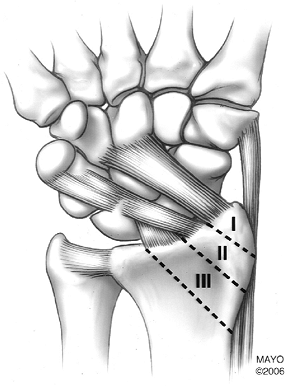

Radial styloid fractures are divided into

three zones. Zone I fractures may be stable without associated ligament

injuries. Zone II fractures commonly have associated ligament injury.

Zone III fractures are likely to have ligament injury and joint

incongruency (Fig. 9-6). -

![]() |

FIGURE 9-6

Zones of radial styloid (Barton fracture). Zone I: styloid tip, may be stable with no ligament injury. Zone II: possible ligament injury, may have articular deformity. Zone III: likely to have ligament injury and joint deformity. |